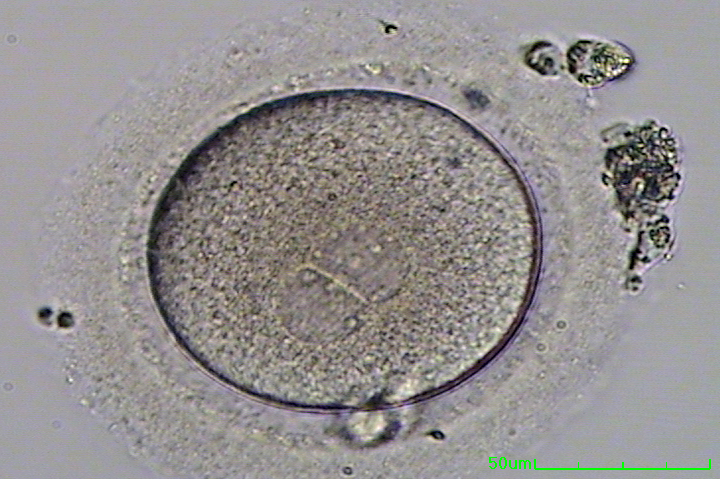

- Check for Maturity: Lab techs look at each egg under a microscope to see if it’s ready to meet some sperm.